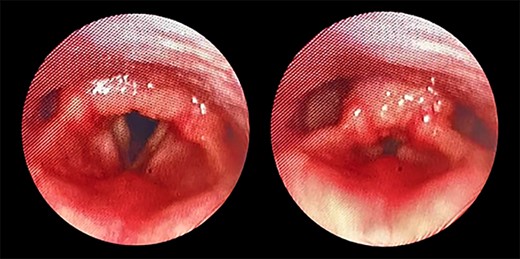

Direct laryngobronchoscopy showing a polypoidal lesion on the middle third of the left vocal fold with a granular appearance of the interarytenoid region and cobblestoning of the posterior pharyngeal wall.

The patient underwent direct microlaryngoscopy (MLS) with multiple biopsies under general anesthesia. MLS revealed the same previous findings with a clear subglottic area (Figs 1 and 2). Multiple biopsies were obtained from the mentioned regions using punch forceps. There were no intraoperative or postoperative complications. The patient was discharged in stable condition the following day.